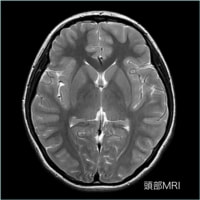

<放射線部の特徴と検査内容>

平成25年より新しく稼働したCT、MRIを始め、マンモグラフィー、骨密度測定、レントゲン画像装置などにより病気の早期発見、早期診断を目指しています。

MRIとは?

MRIとは核磁気共鳴画像法(英語: Magnetic Resonance Imaging)の略です。

核磁気共鳴(nuclear magnetic resonance, NMR)現象を利用して生体内の内部の情報を画像にする方法です。

診断において断層画像という点ではレントゲンCTと一見よく似た画像が得られることが出来ます。

しかし、MRIは強力な磁石を使うことより放射線被曝はありません

また、放射線CTと原理が異なるため、それぞれの特徴を吟味しCTと組み合わせて画像診断を行うことがあります。

軟部組織のコントラストに優れ、様々なコントラストパラメーターを有するMRIは、頭頚部、体幹部、脊椎・脊髄、整形領域、心臓領域とほぼ全身に渡る断層画像をあらゆる角度で撮像できます。

MRIの画像